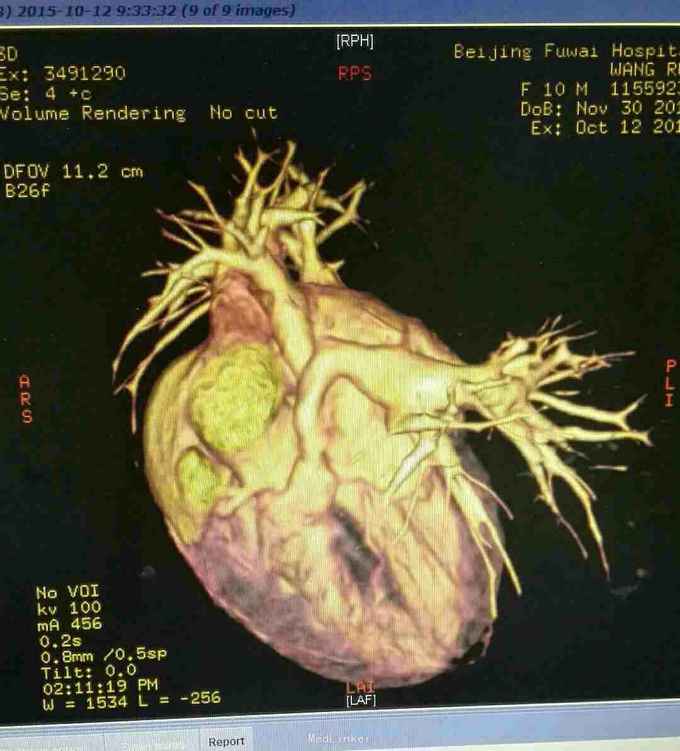

查体 生命体征平稳,口唇发绀,双肺呼吸音清,未闻及干湿性罗音,心律规整,于胸骨左缘可闻及杂音,腹部平软无压痛反跳痛,双下肢无水肿。 辅助检查结果 心脏彩超示 先天性心脏病 法乐氏四联症 肺动脉发育不良 左肺动脉 0.65mm,右肺动脉 0.49mm。 心脏CT检查结果示 先天性心脏病 法乐氏四联症 肺动脉发育不良

先天性心脏病 法乐氏四联症 治疗 患者入院后完善各项术前检查及准备,排除手术禁忌症后为患儿行跟手术治疗。 手术过程 全麻成功后,常规消毒,胸骨正中切口,常规建立体外循环,降温阻断升主动脉后,心脏停跳,切开右房,经卵圆孔放置左心引流,经右心室流出道切口,切除肥厚的隔束及壁束,切开肺动脉瓣交界处粘连,可通过9号探子,左右肺动脉可通过7号探子,取涤纶补片修补室间隔缺损,已带瓣牛心包补片加宽右室流出道,开放循环,心脏复跳,手术过程顺利,患者安反监护室。